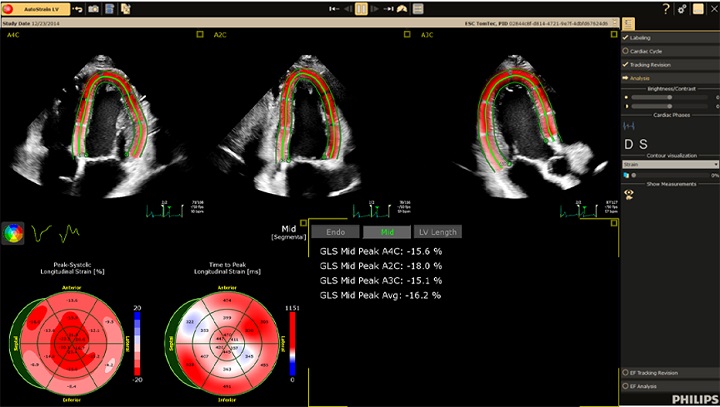

AI を活用したストレイン解析 AutoStrain LV に、AI による最適な 3 断面の選択機能である Smart View Select が加わり、検査中に必要な 3 断面が保存されると 1 ボタンでストレイン解析を開始することができます。また、Mid Layer のストレイン解析、Auto EF 算出にも対応し、迅速かつ高い再現性で多くのパラメーターを得ることができます。このことは多くの検査を実施しなければならない検査室で効率よく信頼性の高い検査を実行することに貢献します。